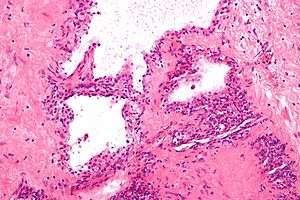

| Micrograph showing a pancreatic serous cystadenoma, a type of cystadenoma. H&E stain. | |